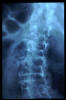

Osteoporosis. Cifosis.